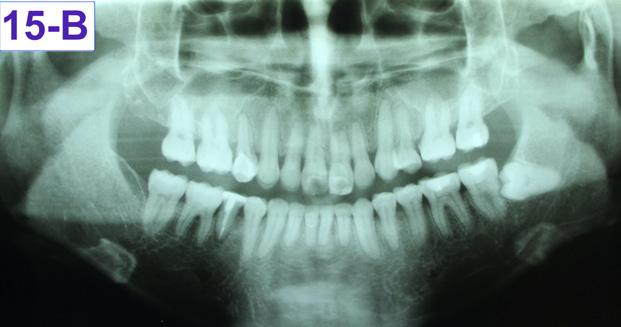

Panoramic radiogram revealed complete permanent dentition with mandibular left impacted wisdom tooth. Roots of the mandibular second bicuspids appeared to be short. There was an excellent bone support and no sign of periodontal or periapical pathology. (Figure 5-B).

FIG. 5B: Pre-treatment, Panoramic radiogram

The final panoramic radiogram reveals impacted mandibular left wisdom tooth, minimal root resorption and acceptable angulation except for #22(10), where the root remained mesially oriented. Root canal therapy was done on the tooth #45(29), because it developed purulent pulpitis during the orthodontic treatment.